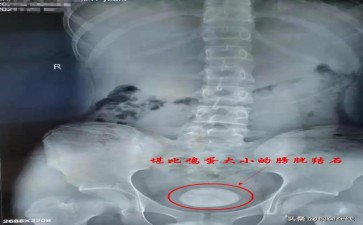

胆囊 “垃圾处理站” 咋堆出 “顽固结石”(哈尔滨北一医院)?在人体的消化 “环保系统” 里,胆囊堪称一座精密的 “胆汁垃圾处理站”,每天接收肝脏生产的胆汁,精心调配后送往肠道,帮助分解脂肪、消化食物,堪称消化 “环卫工”。可不知何时,这座 “处理站” 里竟堆出了 “顽固结石”,搅乱了原本的秩序。

这些 “垃圾顽疾” 的形成,和我们日常 “错误的环保操作” 息息相关。长期顿顿炸鸡烧烤、奶茶蛋糕不离手,就像给 “处理站” 疯狂投递难以降解的 “高胆固醇垃圾”,超出它的处理能力;经常不吃早餐,胆汁在 “站内” 滞留过久,如同垃圾堆积发酵,变质结块;肥胖、糖尿病等健康问题,则像 “处理站” 设备老化、效率下降,让杂质更容易沉积。起初,小结石可能悄无声息 “潜伏”,一旦它们 “兴风作浪”,右上腹会突然传来剧痛,疼得人直冒冷汗,还可能恶心呕吐、看到油腻食物就犯怵,仿佛 “处理站” 因垃圾堵塞引发了 “环保危机”。